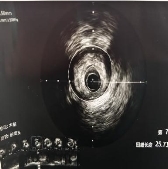

技术亮点:血管内超声,给医生装上一双“透视眼”

术中,刘主任带领团队将一个微型超声探头送入患者冠状动脉血管内。这个探头就像一台“内窥摄像机”,能够实时、高清、立体地呈现血管壁的内部结构——斑块分布在哪、血管真实直径多少、管腔面积多大、病变边界到哪里,全部一目了然。

◆左主干体尾部狭窄约 50%,血管内最小管腔面积 3.35mm^2(正常应大于6mm^2)